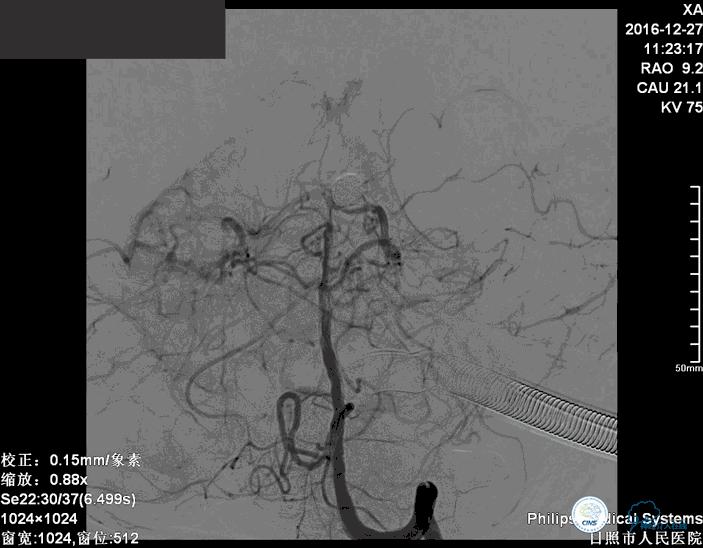

术后

术后患者神志清楚,术后肢体运动较术前未见明显异常。

这个手术的难点是在保证动脉瘤致密栓塞的同时,要保证双侧大脑后动脉的通畅。最终手术达到了较好的效果。

术后患者神志清楚,术后肢体运动较术前未见明显异常。双微管技术降低了患者治疗的费用。同时避免了支架置入以后,终生服用抗血小板药物的情况。